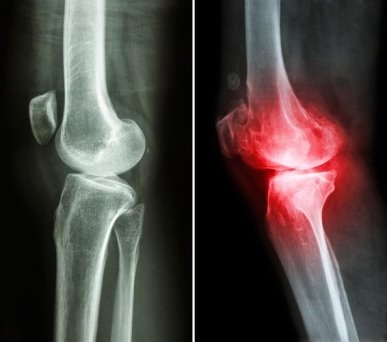

立冬將至,氣溫驟降、濕寒加重,不少人的關(guān)節(jié)開始“鬧脾氣”,酸脹疼痛、僵硬發(fā)麻,甚至活動時還會發(fā)出摩擦聲,陰雨天不適感更甚。這其實是關(guān)節(jié)軟骨磨損后,骨關(guān)節(jié)炎發(fā)出的預警信號,若不及時干預,病情可能持續(xù)進展。想要安穩(wěn)過冬、守護關(guān)節(jié)健康,選對干預方式很關(guān)鍵。而維固力這類OTC硫酸氨糖,便是臨床常用的骨關(guān)節(jié)炎治療藥物,憑借確切療效和高耐受性,成為不少人應(yīng)對秋冬關(guān)節(jié)不適的優(yōu)選。

骨關(guān)節(jié)炎是一種以關(guān)節(jié)軟骨磨損、破壞等為特征的慢性退行性疾病。當失去了軟骨的緩沖,關(guān)節(jié)間直接摩擦,遇寒、受潮時就容易誘發(fā)炎癥。而氨糖是合成軟骨細胞的核心原料,也是構(gòu)成軟骨基質(zhì)與關(guān)節(jié)液的基礎(chǔ)成分。它不僅能修復受損軟骨組織,還可補充關(guān)節(jié)滑液,降低摩擦,同時通過抑制關(guān)節(jié)腔內(nèi)的炎癥因子,有效延緩骨關(guān)節(jié)炎的發(fā)展進程[1]。

同時,維固力能夠有效緩解關(guān)節(jié)不適這一點,得到了世界頂級醫(yī)學期刊《柳葉刀》的證明?!读~刀》一項研究表明,治療膝骨關(guān)節(jié)炎時,長期服用維固力可顯著減輕關(guān)節(jié)疼痛程度約4倍[3],提升關(guān)節(jié)功能指數(shù)約2倍[4],延緩關(guān)節(jié)間隙變窄的程度約4倍[5],從根源改善關(guān)節(jié)結(jié)構(gòu),延緩關(guān)節(jié)磨損。